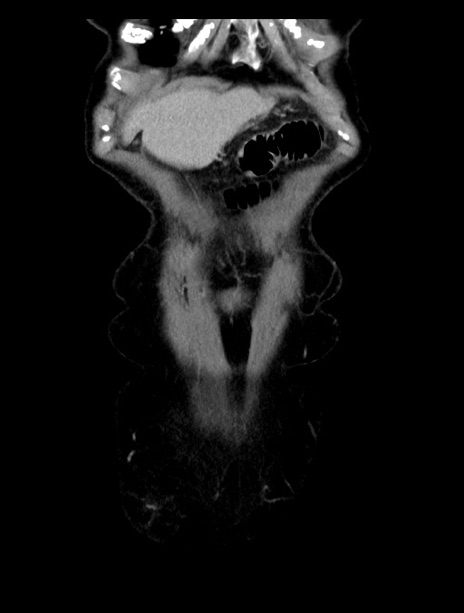

症例23(冠状断像)

【症例】70歳代女性

【主訴】下腹部痛・嘔吐

【現病歴】2日前より腹痛あり。昨日嘔吐あり。症状改善しないため来院。

【既往歴】胃GISTに対して胃部分切除後。

【身体所見】BT 37.1℃、BP 128/77mmHg、腹部:平坦・軟、下腹部に圧痛あり。

【データ】WBC 10200、CRP 0.31